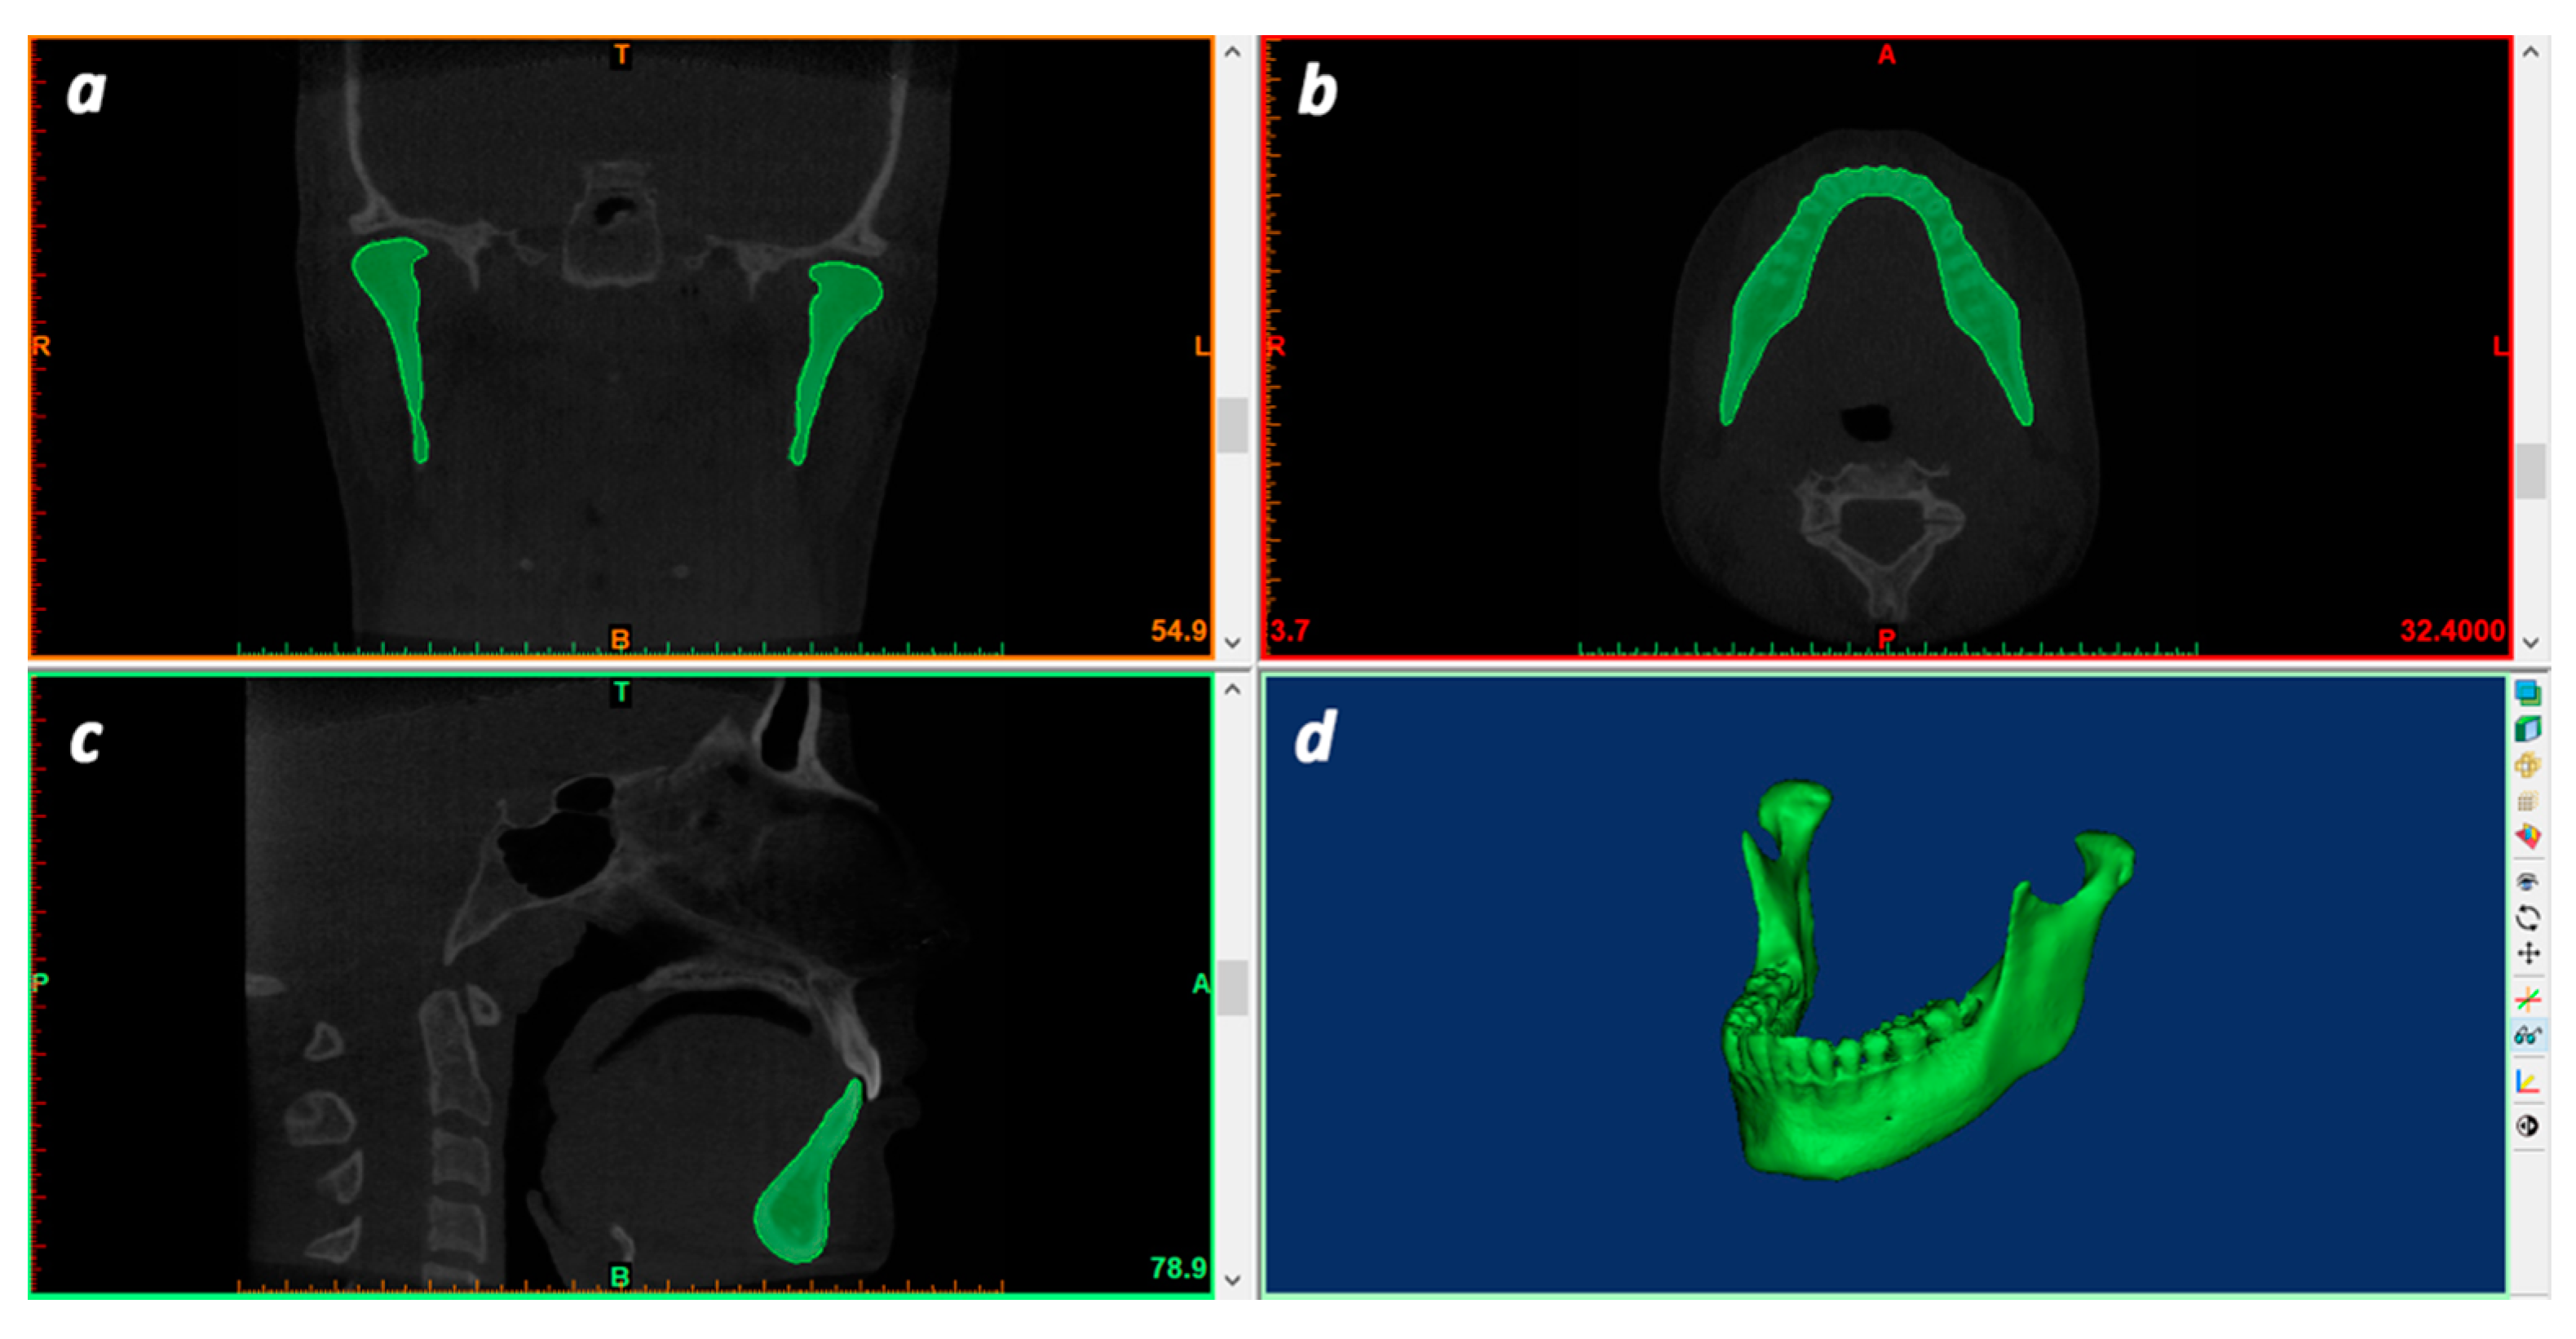

2. Materials and Methods